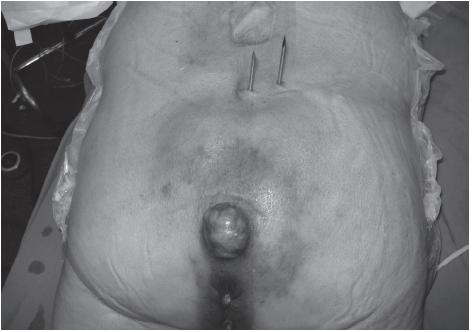

Experiências como a de Gennari et al. (14) mostraram a factibilidade da ressecção com o acesso posterior exclusivo, em uma série de 8 casos. Na escolha da via de acesso, a abordagem abdominossacral tem se mostrado segura e de melhor exposição da lesão (7-15). Nós preferimos o duplo acesso, iniciando por abordagem abdominal que nos permite realizar o controle vascular, liberação retal e dos ureteres distais, além da marcação do ponto de transsecção proximal do sacro (Figura 3).

Fig. 3 - Aspecto posterior da marcação de osteotomia sacral proximal, com hastes metálicas, colocadas durante tempo abdominal, para facilitar a exata transsecção sacral durante o tempo posterior.